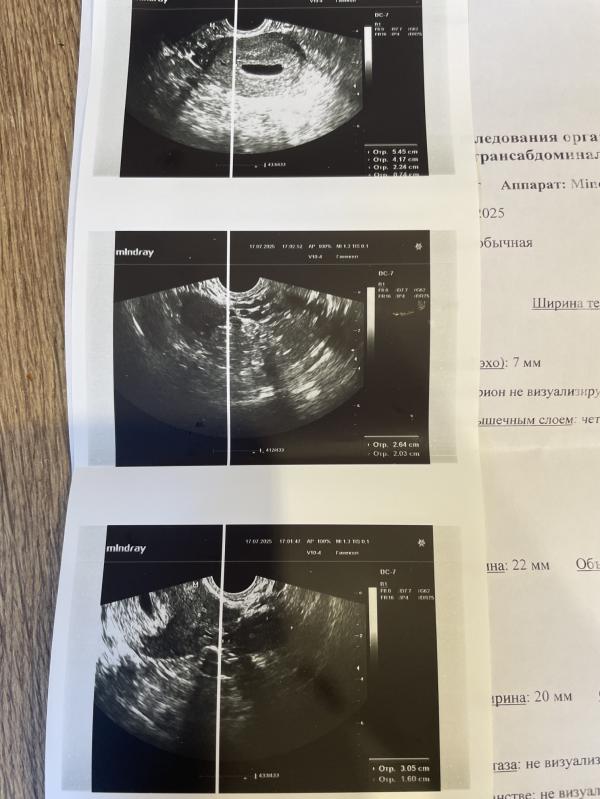

Увидели только плодное яйцо, эмбриончика нет. Может быть кто-то сталкивался с таким явлением и все было хорошо? Накрутила себя уже до невозможного

Посмотрите развитие в динамике дней через 10. И лучше в другой клинике. Здесь почему-то в информации по яичникам нет данных о желтом теле. Непонятно видит она его или нет и в каком яичнике. Оно там, где овуляция была.

Если через 10 дней будет желточный мешочек, а эмбриона так и не увидят, то сходить еще позднее на повторное узи. Вероятна поздняя овуляция, если по срокам не будет совпадать.